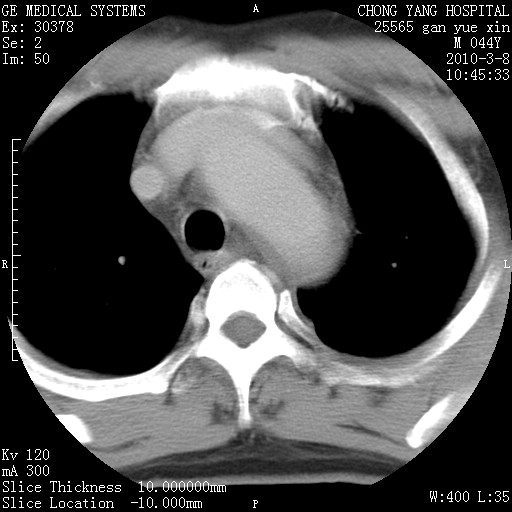

标题: CT24940:主动脉增强,典型病例。 [打印本页]

标题: CT24940:主动脉增强,典型病例。

夹层动脉瘤。

动脉夹层

夹层动脉瘤,典型

主动脉夹层。

动脉夹层的分型:

⒈debakey分型:根据主动脉夹层累及部位,分为三型:ⅰ型:原发破口位于升主动脉或主动脉弓部,夹层累及升主动脉、主动脉弓部、胸主动脉、腹主动脉大部或全部,少数可累及髂动脉。ⅱ型:原发破口位于升主动脉,夹层累及升主动脉,少数可累及部分主动脉弓。ⅲ型:原发破口位于左锁骨下动脉开口远端,根据夹层累及范围又分为ⅲa,ⅲb。ⅲa型:夹层累及胸主动脉。ⅲb型:夹层累及升主动脉、腹主动脉大部或全部。少数可累及髂动脉。

⒉stanford分型:a型:夹层累及升主动脉,无论远端范围如何。b型:夹层累及左锁骨下动脉开口以远的降主动脉。

夹层动脉瘤,少量胸水

夹层动脉瘤;左侧少量胸腔积液。

典型主动脉夹层。